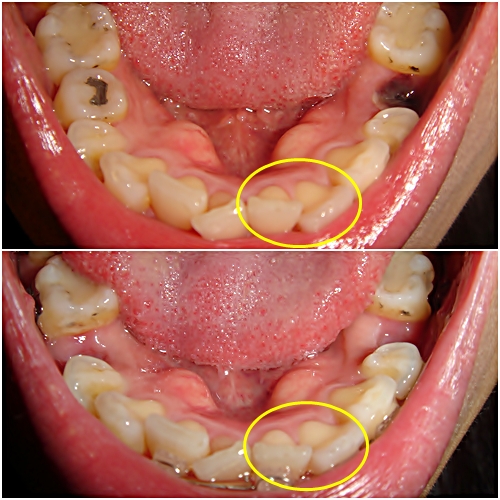

아래 장치 붙인지 딱 1주일 됐는데...

벌써부터 치아의 변화가 느껴져요~ @_@ 이거 너무 빠른 거 아닌지.. ㅎㄷㄷ;;

각도의 미묘한 차이 때문에 달라진 거 처럼 보이는 걸까요? +ㅁ+

어떤가요? 조금 달라진 거 같지 않나요~!? 각도는 거의 비슷한 거 같은데.. ^^;

이렇게 일주일 만에 달라지는 분들이 많은가요~? 'ㅁ')a

치아 이동하는 게 눈에 보이니 신기하기도 하고~ 막 들떴어요 ㅋㅋㅋ

근데 이동하는 게 너무 빠르면 부작용(?)이 생기지 않을까 살짝 걱정되는데.. -ㅁ- )